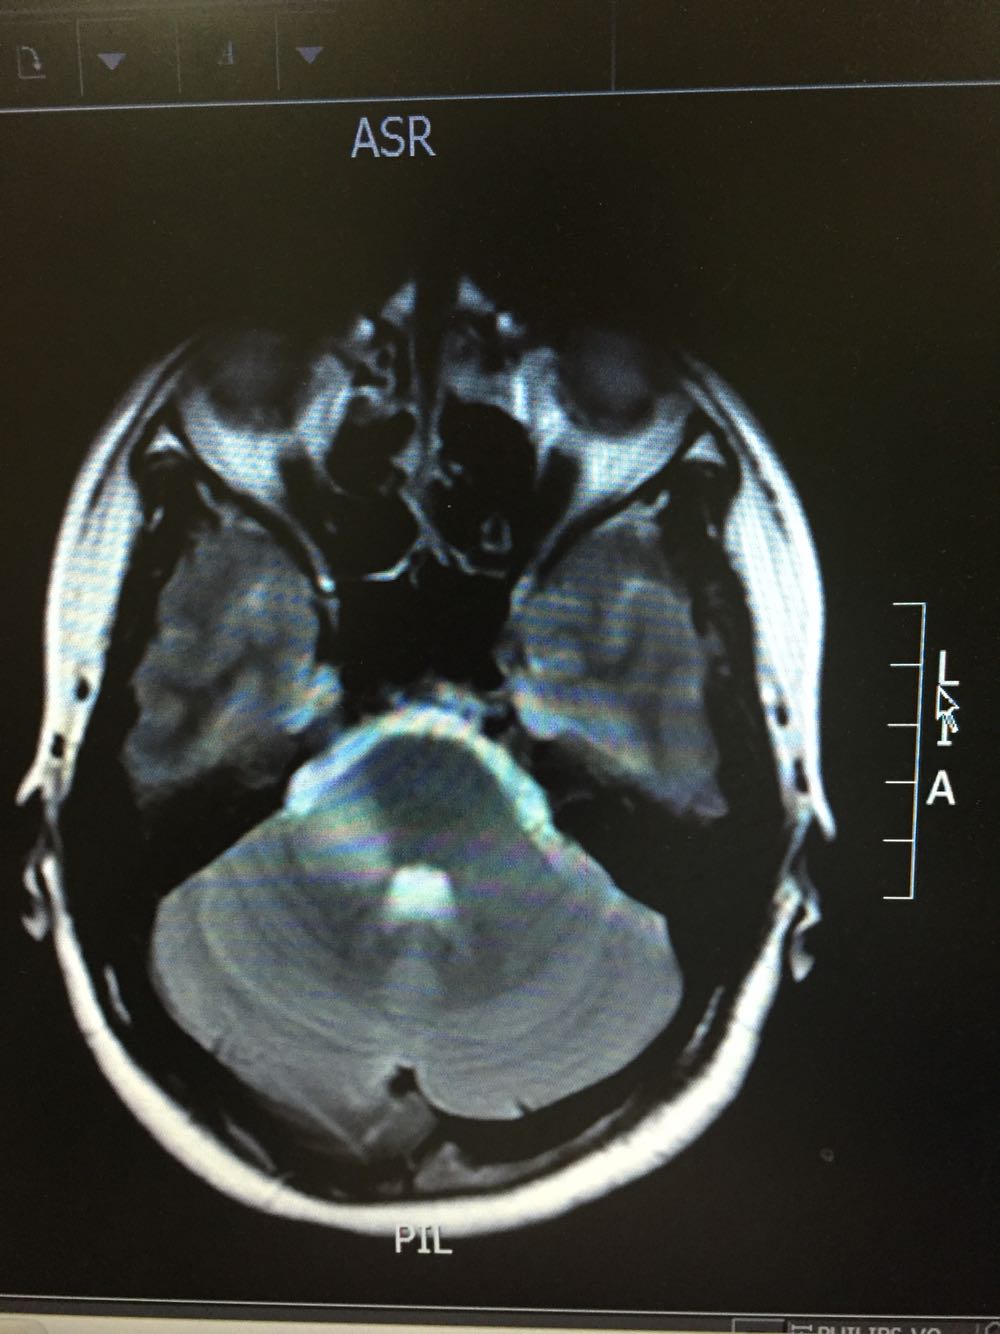

女,35岁,因“右侧肢体无力伴语笨9日”由门诊收入病房。病例特点:1.既往史:青年女患,既往否认高血压病史,否认糖尿病及冠心病史,否认药物、食物过敏史。2.现病史:该患者于入院前9日始出现右侧肢体无力,伴语笨,伴有恶心、呕吐,不伴有头痛,偶有头晕,不伴有尿便障碍,不伴有抽搐发作,为求进一步诊治而来我院。

查体:体温:36。5℃,脉搏:70次/分,呼吸:18次/分,血压:121/79mmHg,神志清楚,言语流利,查体合作,双侧瞳孔等大同圆,对光反射存在,双眼活动自如,鼻唇沟对称,伸舌居中,右侧肢体肌力4级,肌张力正常,腱反射对称,双侧感觉对称,右下肢Babinski征(+)、Chaddock征(+)、颈强(-),克氏征(-)。 脑脊液免疫球蛋白A0.003g/L 抗酸杆菌、墨汁染色阴性,余脑脊液化验未见异常。脑脊液外观无色透明

桥脑脱髓鞘病变可能性大甲强龙冲击治疗

初始考虑青年脑梗死待磁共振增强回报后考虑能否占位可能脑功能成像及脑脊液结果回报后考虑桥脑脱髓鞘病变可能性大,给予甲强龙冲击治疗,冲击治疗后患者症状逐渐好转,右侧肢体肌力出院时5-级。